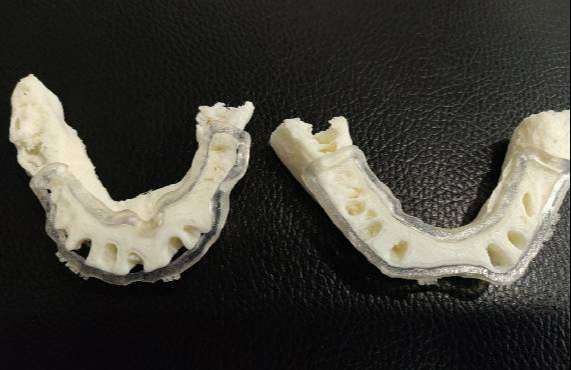

CTARS IPS has a custom made software which can able to guide an implantologist to place an implant in a predetermined surgical plan which will be more precise and accurate to the deep insight about patient anatomy and also helps in reducing the time duration and increasing patient comfort.No two patients teeth are the same. That’s why each and every CTARS IPS guide is custom made to fit your implant plan and patient’s anatomy.CTARS is available with tooth or bone (dentulous or edentulous) supported.

One Guide KIT

Pilot Drill Guided